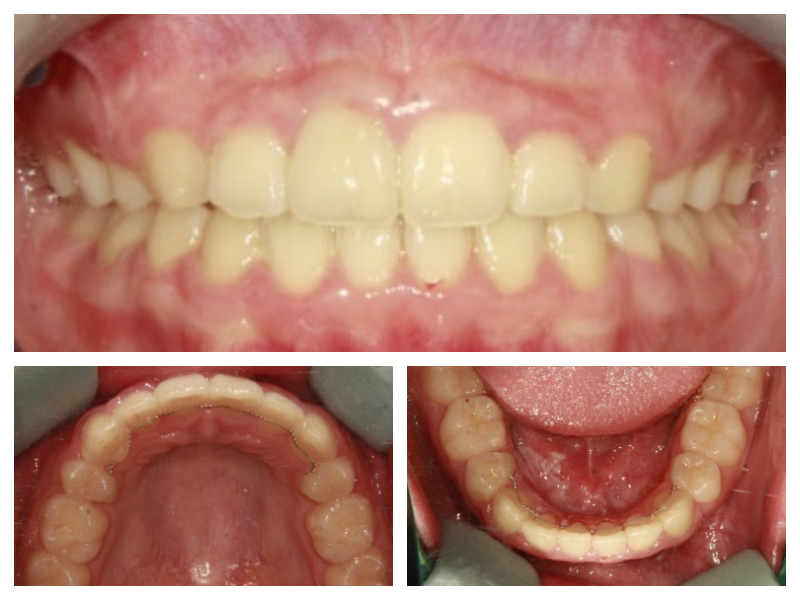

돌출입교정

돌출과 비대칭 교정치료